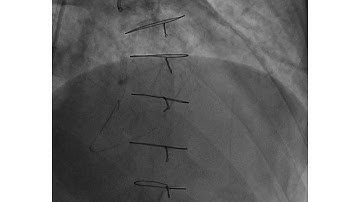

Case 90: Manual of CTO Interentions: Adventurous ostial RCA CTO recanalization